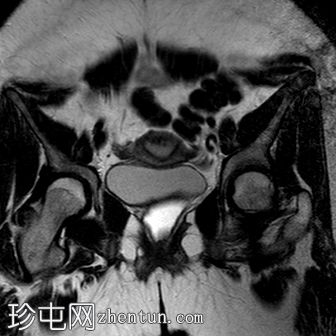

冠状位

T2加权像

阴道明显扩张,T1加权像呈中高信号,T2加权像呈高信号,耻骨联合下方可见一小局灶性隆起。

右侧卵巢可见一圆形、边界清晰的囊肿,最大轴位径为4.2 x 4.3 cm,T1加权像呈低信号,T2加权像呈高信号。

左侧卵巢大小正常,可见一小出血性囊肿。